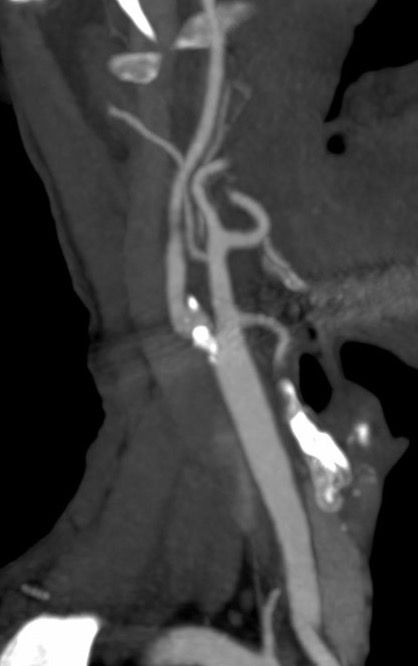

In >2,400 patients with ≥70% asymptomatic carotid stenosis on optimised modern medical therapy, adding carotid stenting almost halved the 4‑year risk of stroke/death vs. medical therapy alone (≈6.0% → 2.8%), with a number needed to treat of ~31 to prevent one primary outcome event over 4 years.

In the endarterectomy trial, intensive medical therapy alone performed so well that CEA did not reach a statistically significant additional benefit: 4‑year primary‑outcome rates were ≈5.3% with medical therapy vs. ≈3.7% with CEA, with a small absolute difference and overlapping confidence intervals.

– The clearest incremental benefit in CREST‑2 was seen with stenting plus best medical therapy, while CEA showed only a modest, statistically non‑significant numerical advantage over medical therapy alone.

– All of this was achieved in expert, high‑volume centres with rigorously credentialed operators and very low peri‑procedural complication rates.